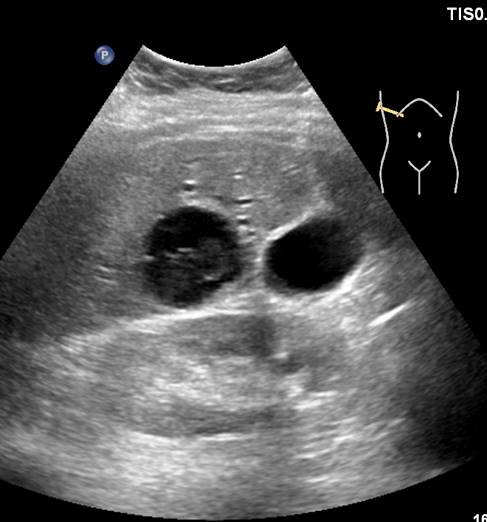

Представлены клинические наблюдения редкого осложнения эхинококкоза печени – прорыва эхинококковой кисты в желчные протоки. Осложнение стало причиной обструкции желчных протоков, механической желтухи и холангита. Освещены этапы диагностики, роль УЗИ в выявлении осложнений эхинококкоза печени, рассмотрены способы минимально инвазивного лечения с применением эндоскопических и чрескожных технологий под контролем лучевых методов.